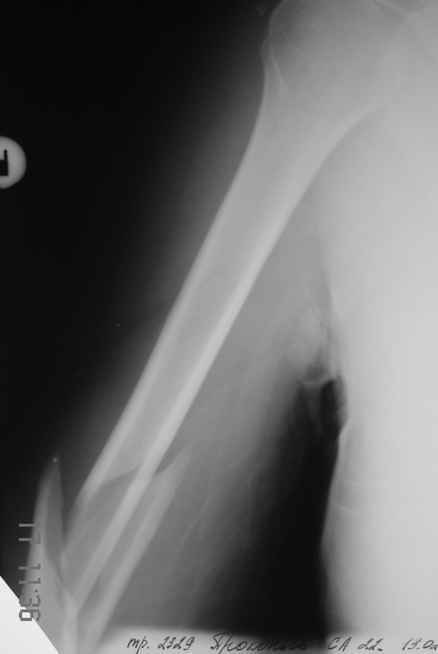

Огромное спасибо всем принимающим участие в дискуссии. Вначале отвечу на поступавшие персональные вопросы: 1. обстоятельства травмы - соревнования по армрестлингу (от себя замечу, что у военных нередкая травма в последнее время! На мой взгляд это связано с вовлечением в это дело неподготовленных людей - командирам нравится, т.к. в плане реквизита намного легче организовать чем традиционное перетягивание каната...). 2. в отношении провокационной составляющей - она присутствует, но лишь в той степени в какой любое инициирование дискуссии несет в себе элемент провокации... 3. про актуальность консервативного лечения - мне кажется это актуально всегда и при любой локализации если врач владеет методом, например, часто наблюдал великолепные функциональные результаты консервативного лечения переломо-вывихов голеностопных суставов... Тут только надо помнить, что "консервативное" это тоже лечение (контроль, тяги, перекладывание повязок), а не просто накладываем гипс и через энное время говорим, что не получилось и берем на операцию.

Теперь непосредственно по больному. Лечим функциональной повязкой, добились вот чего (приложение). Будем признательны за дальнейший комментарий - мое мнение, что можно продолжить без операции.